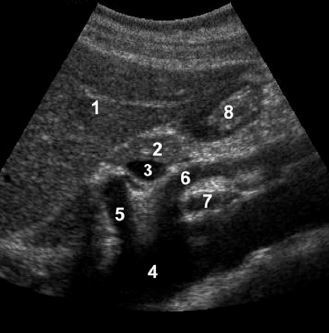

1. left lobe of liver

2. pancreas

3. porto-splenic confluence

4. aorta

5. IVC

6. SMA

7. CBD

8. gastroduodenal artery

The CBD travels in the most posterior aspect of the

pancreas. In fact, it often appears immediately anterior

to the IVC. The gastroduodenal artery arises from the

common hepatic artery and descends along the anterior

aspect of the head of the pancreas. These two structures

often appear as two small anechoic dots on transverse

views of the pancreatic head.